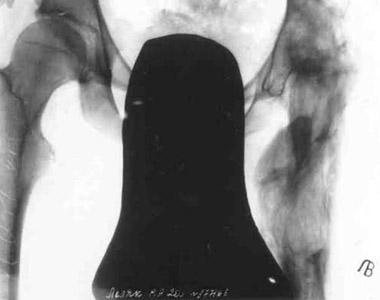

After elongation of the hip.